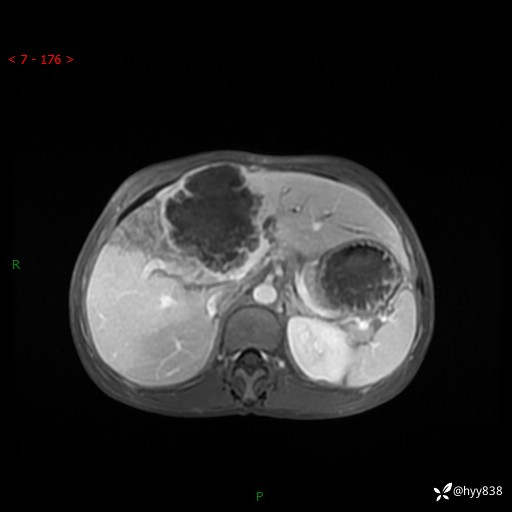

【患者信息】:58岁/男

【主诉】:发现肝占位2天

【现病史及既往史】:患者2天前于当地市第五医院查上腹部磁共振提示:肝脏S4段占位性病变,肝ca可能,胆囊结石,腹膜后多发肿大淋巴结,无剑突下及右上腹疼痛不适,无明显反酸、嗳气,无畏寒、头晕、头痛,无尿频、尿急、尿痛等不适,今为求进一步治疗特来我院就诊,门诊以“肝占位”收住我科。 患者病程中精神、睡眠、饮食尚可,大小便正常、体力体重无明显变化

【检查】:肝脏MRI】平扫+增强